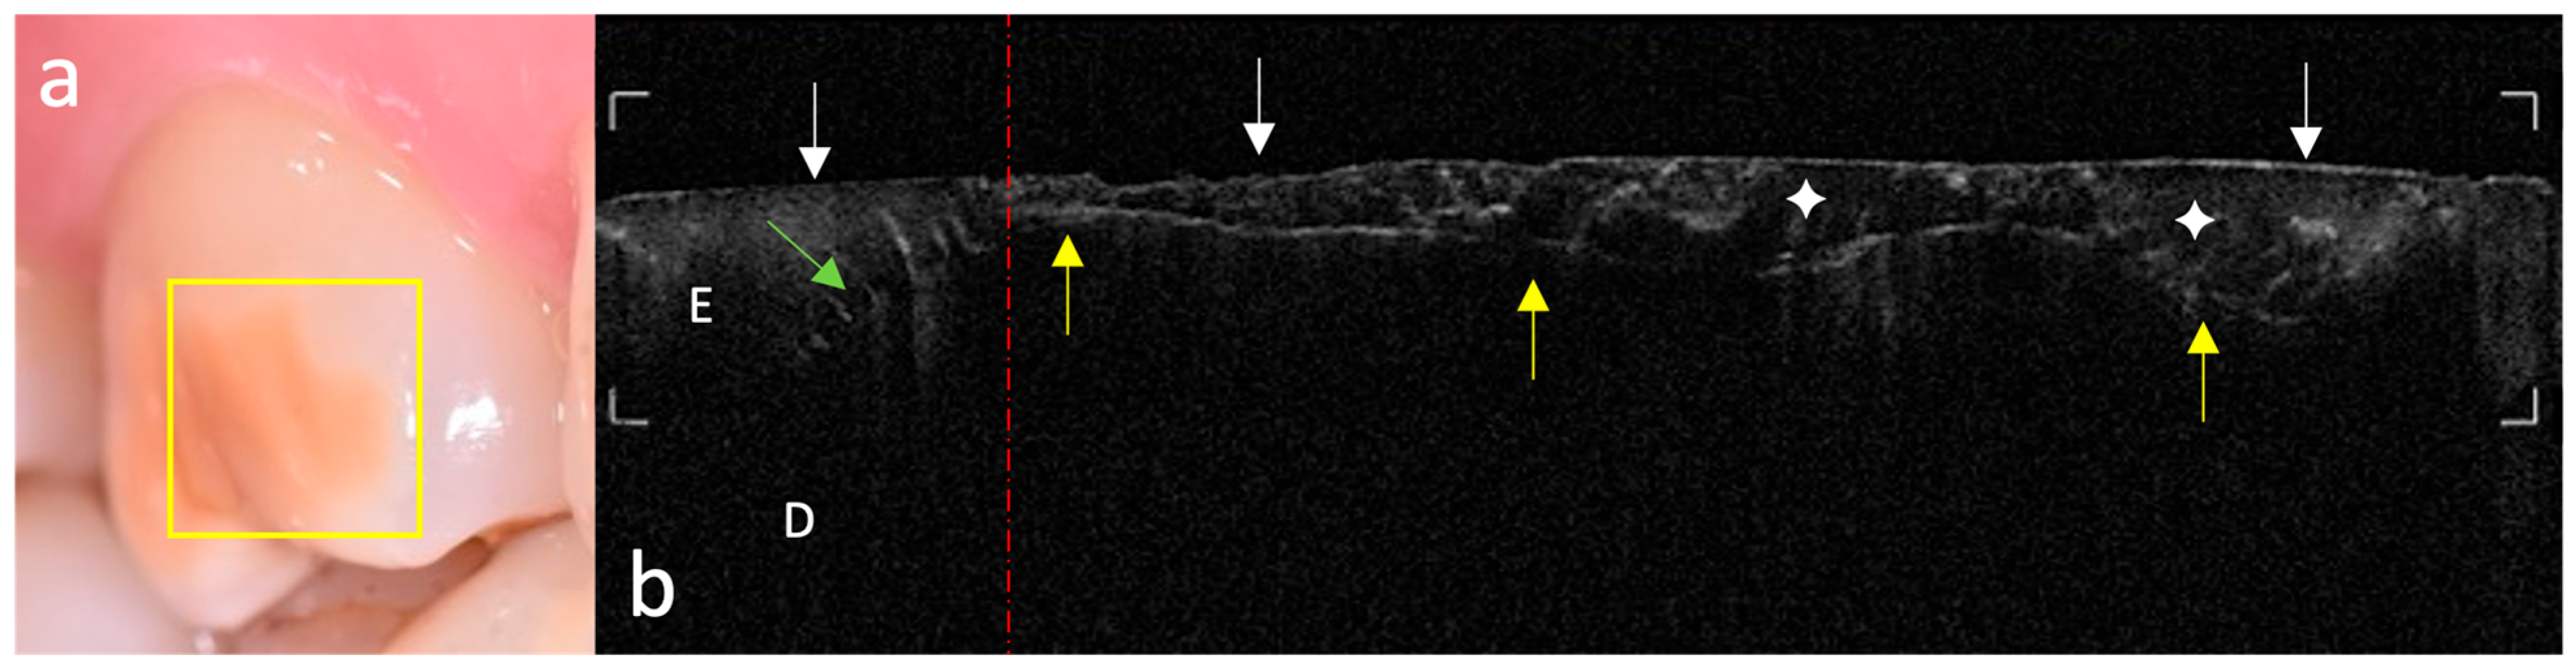

A structurally complex pattern characteristic of mild MIH highlighted how the clinically intact appearance of the enamel surface may mask internal alterations detectable only by high-resolution imaging (Figure 4). In the presence of a macroscopically continuous surface, OCT scans revealed vertical hypo-reflective lines extending from the outer surface toward the DEJ, consistent with microcracks. These discontinuities were associated with underlying conical shadowing, indicative of disrupted optical coherence due to subsurface fractures. In the same context, the DEJ appeared blurred and lacked its typical continuous hyper-reflective profile, suggesting early disruption of the enamel–dentin interface. The superficial enamel layer exhibited a heterogeneous hyper-reflective band consistent with hypomineralization, overlying a deeper hypo-reflective zone interpreted as subsurface porosity. While morphologically continuous, the enamel surface presented an altered and heterogeneous optical profile, in line with a latent structural vulnerability.

Another representative pattern observed in mild MIH-affected teeth was characterized by a sharply demarcated internal discontinuity within the enamel, not associated with a vertical fracture but with a horizontal separation between two structurally distinct optical domains (Figure 5). OCT scans revealed a well-defined hyper-reflective line located beneath the enamel surface, delineating a disorganized superficial layer from a homogeneous hypo-reflective deeper region. A transition zone, demarcated by a vertical red dashed line, separated the left portion of the scan—where a regular enamel–dentin structure with well-defined enamel tufts was visible—from the disorganized and optically altered right region. This configuration is compatible with a mineral discontinuity interface, potentially reflecting early structural delamination or incomplete prismatic maturation during amelogenesis. This internal separation was accompanied by a poorly defined DEJ and marginal enamel areas with increased reflectivity, suggesting localized susceptibility to mechanical stress.

Figure 4. Vertical enamel microcrack with associated conical shadowing and OCT signal heterogeneity. (a) Clinical photograph: the vestibular enamel surface shows a sharply demarcated white opacity without clinically visible discontinuities. The yellow rectangle marks the area scanned by OCT. (b) Corresponding OCT image: the enamel surface (white arrows) appears morphologically continuous, although optically altered in the affected region. The enamel (E) shows a disorganized hyper-reflective area (#) in the superficial layer, overlying a deeper hypo-reflective zone (white circle, ○) indicative of internal porosity. A vertical microcrack (red arrow) is associated with conical shadowing extending through the enamel and into the dentin (D). The dentino–enamel junction (DEJ) is visualized as a continuous and well-defined hyper-reflective line along the scanned region, but appears locally interrupted beneath the shadow cone caused by the microcrack.

Figure 5. Internal enamel discontinuity and superficial OCT reflectivity disruption across a structural transition zone. (a) Clinical photograph: the vestibular surface appears clinically intact, with a well-defined yellowish opacity in the mesial region. The yellow rectangle marks the OCT acquisition area. (b) Corresponding OCT image: the enamel surface appears irregular, non-linear, and fragmented (white arrows), despite the absence of clinically visible discontinuity. A vertical red dashed line identifies the transition between a structurally regular region on the left, where the enamel–dentin interface and tufts are clearly visible (green arrow), and a disorganized, optically altered region on the right. A hyper-reflective but undulating line (yellow arrows) is observed beneath the surface, representing a separation plane between two structural domains. The dentino–enamel junction (DEJ), separating enamel (E) and dentin (D), remains poorly visualized, only in the left sound hard tissues. The overlying enamel layer displays disorganized reflectivity (white four-pointed star, ✧), with alternating hypo- and hyper-reflective zones, conferring a “frosted-glass” appearance consistent with widespread optical alteration.